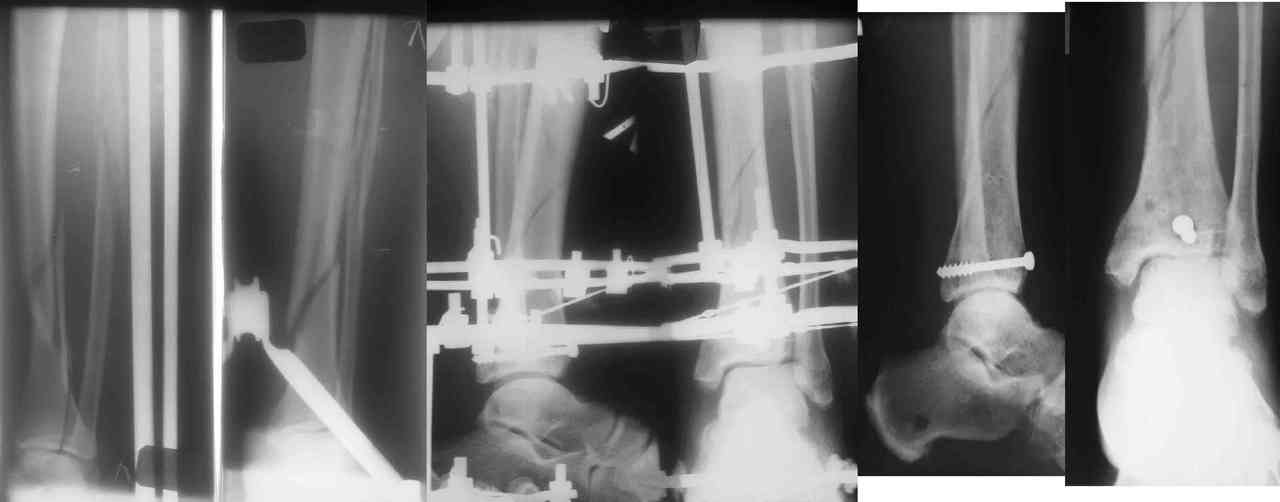

Пример -

задний край и диафиз

3. Последнее время всё чаще делаем аппарат Илизарова в симбиозе с винтами, которыми фиксируем края (передний и задний), лодыжки и теперь - диафиз.

Позволяет пораньше снять аппарат.